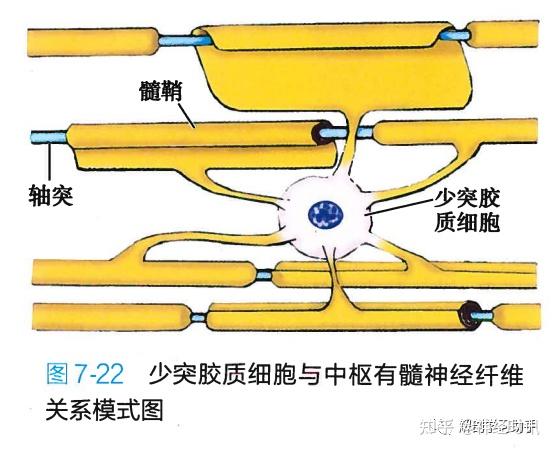

参与形成中枢神经系统有髓神经纤维的髓鞘.